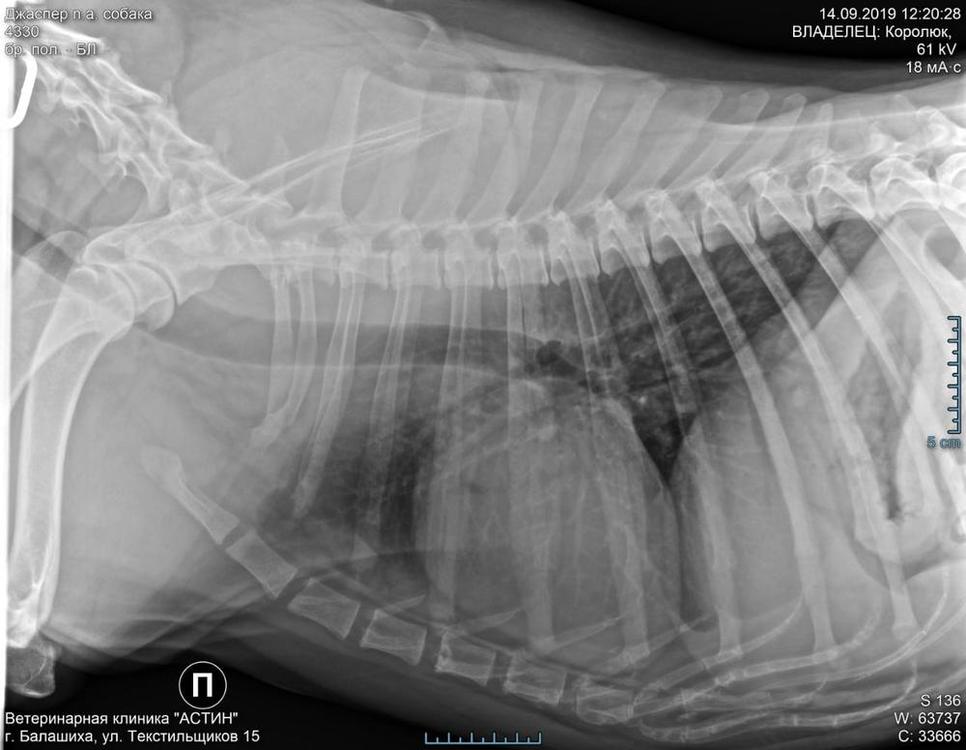

alkor17 Опубликовано 14 сентября, 2019 Автор Опубликовано 14 сентября, 2019 Мы побывали сегодня с Юлей и Джаспером в клинике. Провели практически комплексное обследование. Проблем выявлено достаточно много, к сожалению. На фоне застарелого аллергического процесса есть проблемы и с ушками и с лапками, и сильное воспаление в паранальных железах. Всё в достаточно запущенном, хроническом состоянии. Того, что было назначено летом в Александрове для лечения отита, было совершенно недостаточно, к сожалению, просто сняли острое состояние. Сердце проверили, сделали ЭКГ и Эхо. Ничего криминального, есть небольшие возрастные изменения. Причина кашля, который периодически беспокоит Джаспера - хронический бронхит, опять же застарелый. Это показал рентген грудной клетки ((( Сделали дополнительно УЗИ, так как доверять, сделанному в Александрове уже сложновато. Там не нашли селезёнку, а она на самом то деле есть и довольно прилично увеличена в размерах ((( И это ещё не всё ((( Оба тазобедренных сустава в плачевном состоянии, сильнейший артроз ((( Это естественно не лечится до выздоровления. Тем более в таком солидном возрасте. Но боль при ходьбе это причиняет сильную и постоянную, поэтому лечение назначено симптоматическое, оно пока направлено на снятие воспаления и острого болевого синдрома. Вообщем букет приличный, но Джаспер держится молодцом! Он вообще очень умный и обаятельный мужчина Хочу сказать огромное спасибо Насте *Anastasia.tim.psy* за доставку Джаспера утром в клинику. Несмотря на очень дальнее расстояние, Настя доставила нашего джентлемена даже раньше назначенного времени Обратно Джаспера и Юлю отвезла я. Джаспер конечно уже очень ориентирован на Юлю, стоит только ей отойти хотя бы на шаг, всё, Джаспер сразу начинает переживать и её искать. Очень трогательный мальчик

Лотик Опубликовано 18 сентября, 2019 Опубликовано 18 сентября, 2019 Мастоцитома! Нужна финансовая и информационная помощь, ребята! У нас плохие, у нас, к сожалению, очень плохие новости, друзья! По результатам гистологии у Жоры - мастоцитома. Коварное, злокачественное образование, которое довольно быстро даёт метастазы! С учётом данного факта, под сомнение ставится интерпретация ранее полученных данных рентгена и УЗИ. Поэтому нам необходимо показать наши снимки ещё, как минимум, одному специалисту и/или сделать новые ренгенобследования. Кто может помочь дать контакты врачей, кому можно отправить снимки и получить заключение в онлайн режиме с онлайн оплатой? Снимки прилагаю!

Лотик Опубликовано 18 сентября, 2019 Опубликовано 18 сентября, 2019 Диагноз - хронический бронхит, который был поставлен Джасперу предварительно, сейчас под сомнением! Возможно, это и не бронхит вовсе.............. Сейчас проводим лечение и рекомендуется через две недели повторить ренген лёгких... Посмотреть динамику... Если будут улучшения, то значит это подтверждает данные за бронхит.... К врачу нам через две недели. Операция целесообразна только при отсутствии метастазирования. Его нужно главным образом исключить. Нам нужна любая помощь! Опять деньги, транспортировка, ваша поддержка... Нам очень тяжело морально. Помогите нам, пожалуйста!